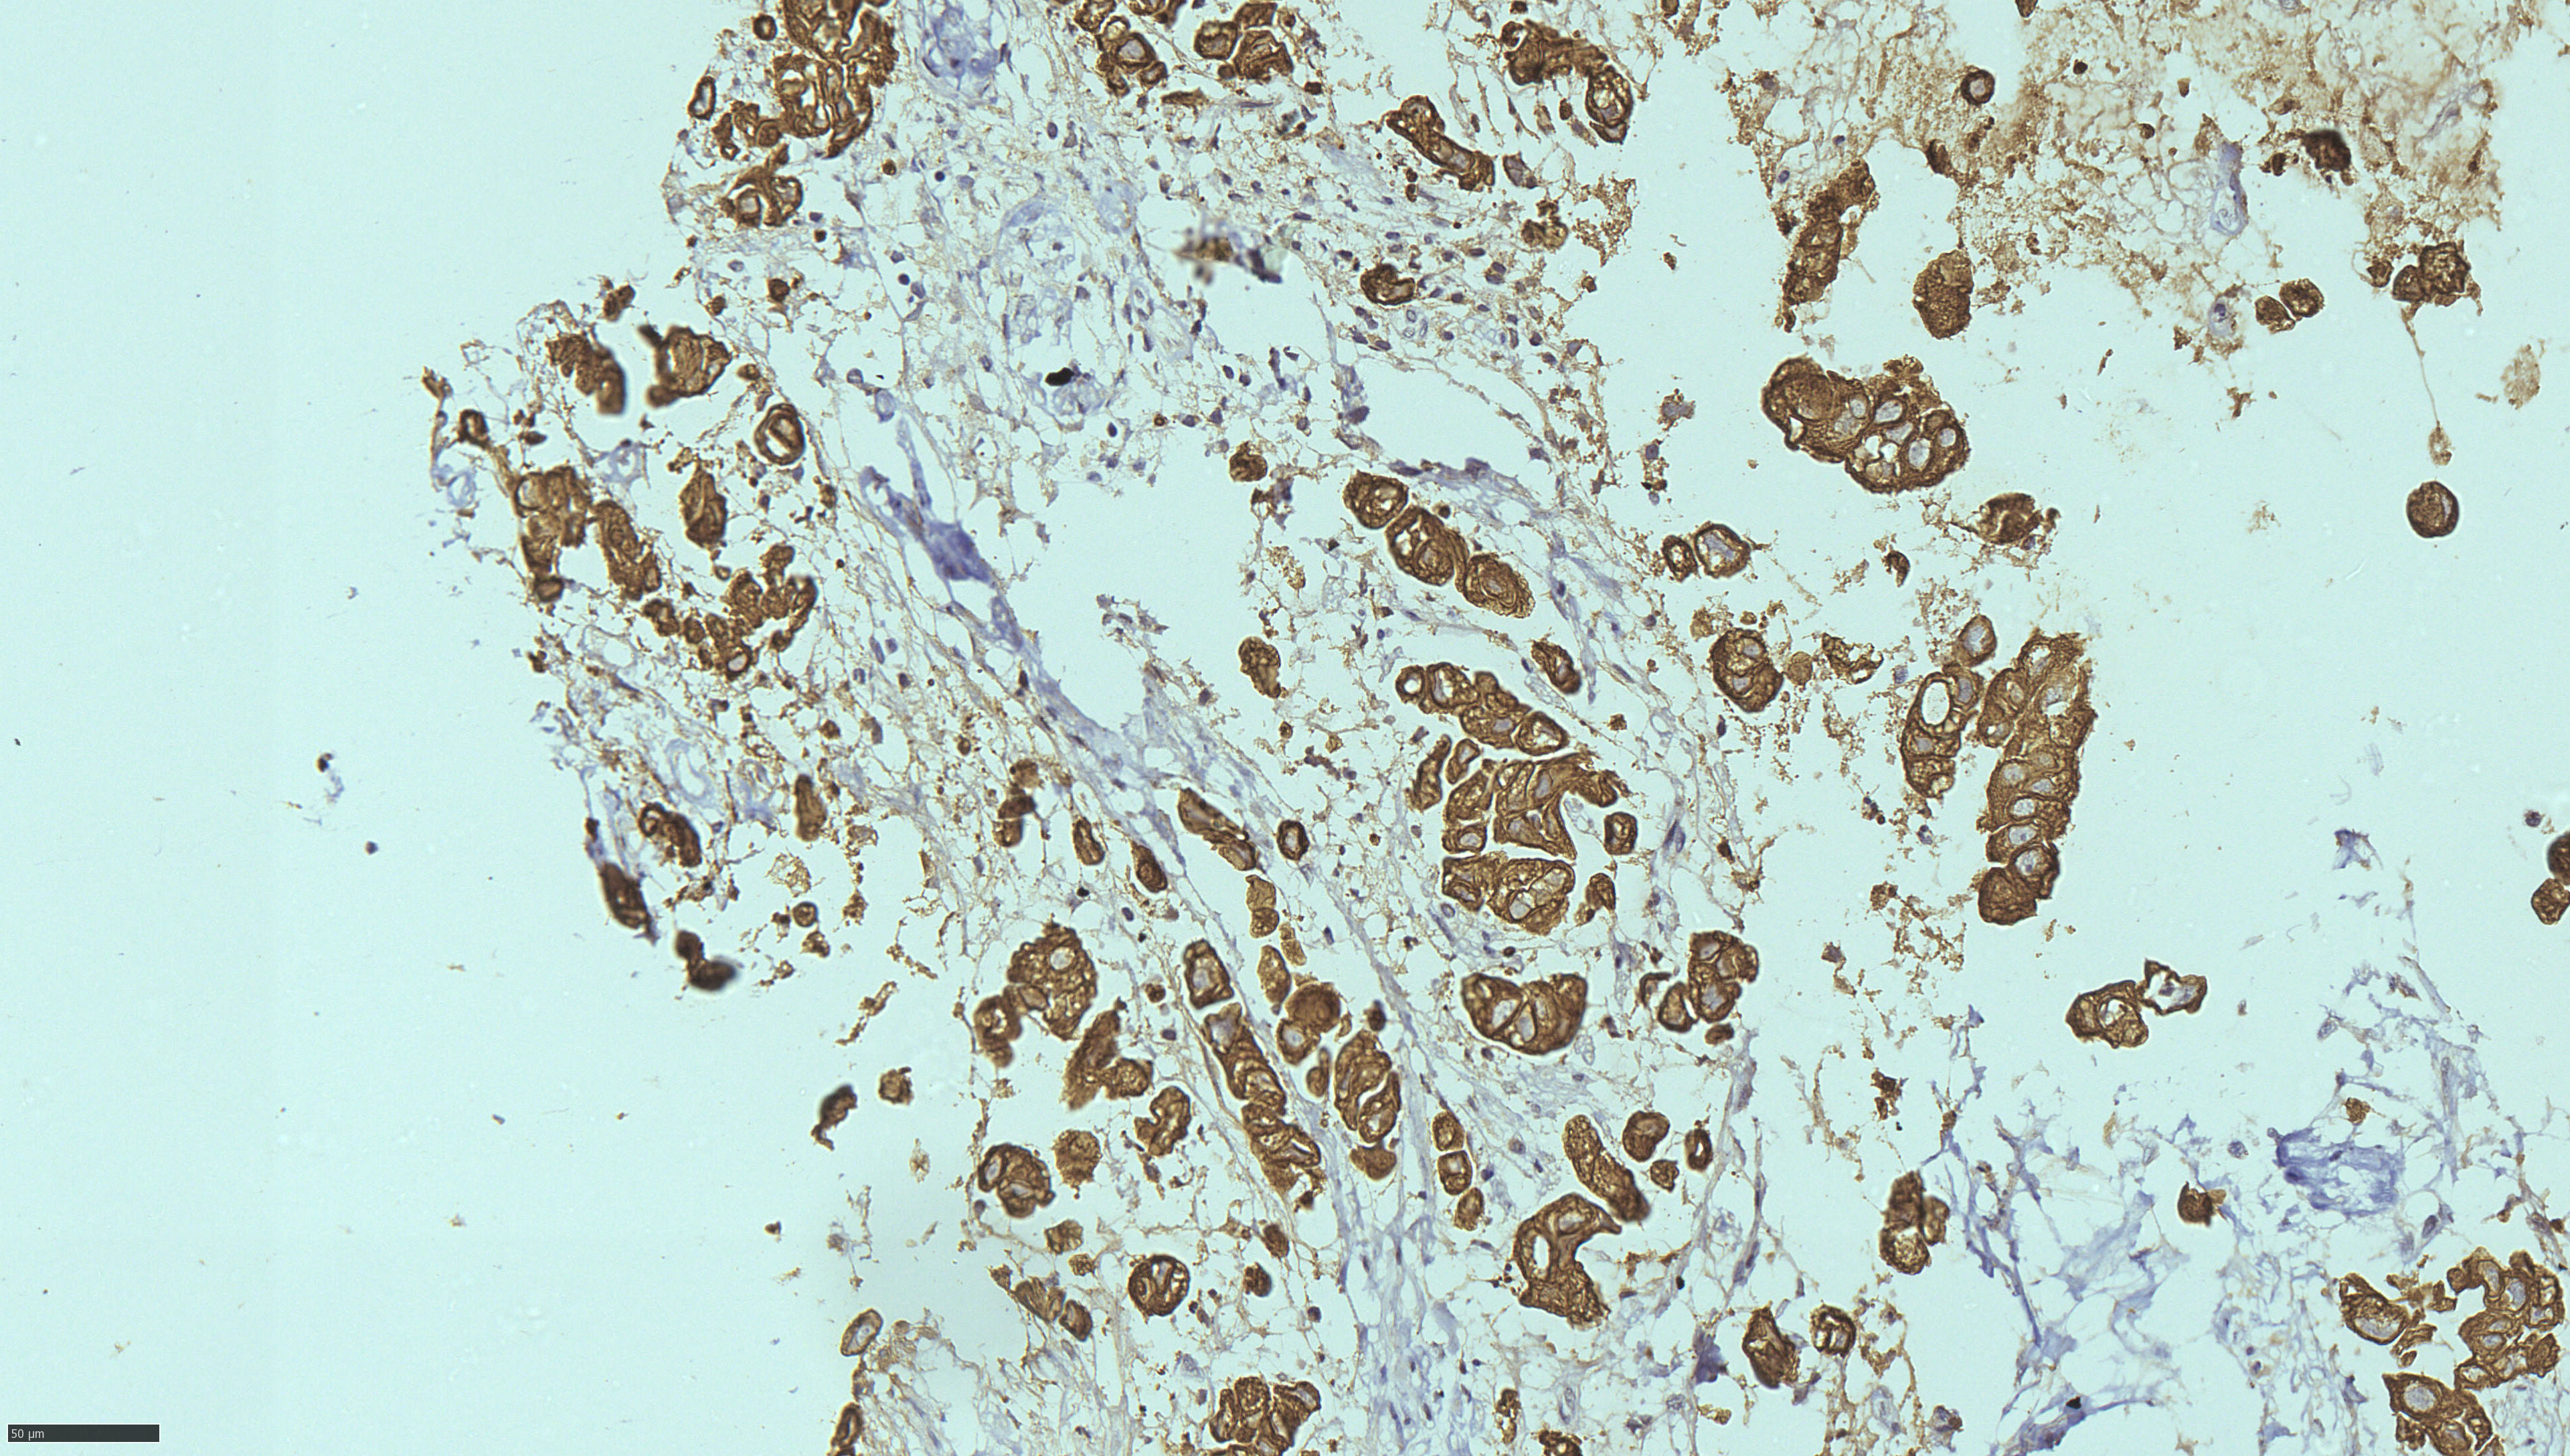

Image Gallery & Slides

Pathology images, lab photos and recent slides. Replace these with higher resolution images from your collection when ready.

To add more images: put your files into the images/ folder and update the <img src="images/yourfile.jpg"> paths below.